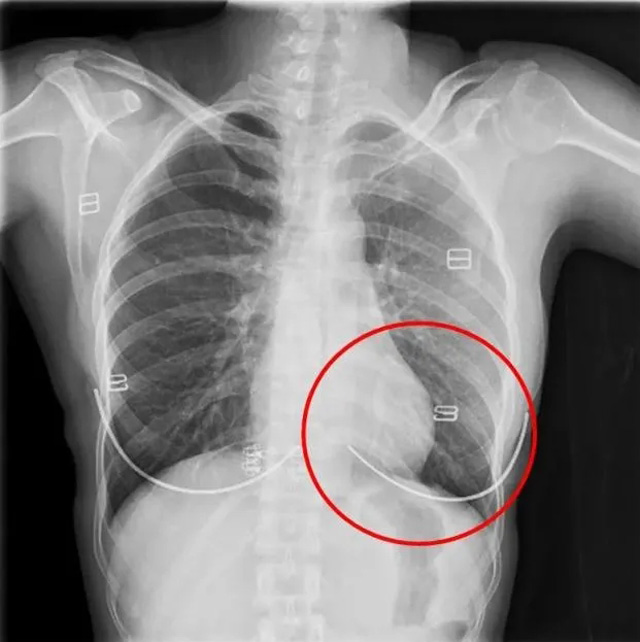

DR是一種比較常規(guī)的基礎影像學檢查方式,適用于人體各部位的健康普查及疾病檢查等優(yōu)勢,在臨床基礎檢查中備受醫(yī)生和患者的青睞。DR體檢車在健康體檢中有著非常重要的地位,由通過電纜串接在一起的探測板、掃描控制器、系統(tǒng)控制及影像顯示器等構成。對比CT檢查而言,DR檢查的價格更低,輻射劑量更小它可以讓疾病預防,微細病變可更好顯示診斷治療提供科學的結果依據。很多外傷患者都要做DR檢查,來判斷是否骨折或其他的情況。體檢過程中面對DR體檢車做檢查時候需要準備注意什么呢?很多時候大家都有這樣的疑問,身上攜帶的物品是否會對圖像造成遮擋或給機器帶來干擾?檢查前如何準備才不會影響檢查準確性?